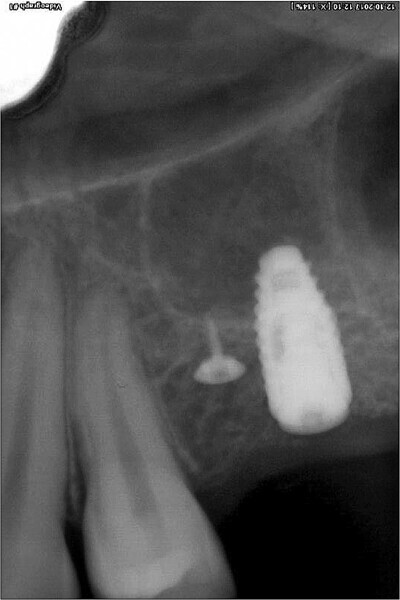

Fig. 1: Initial situation: severe bone defects and implant in situ.